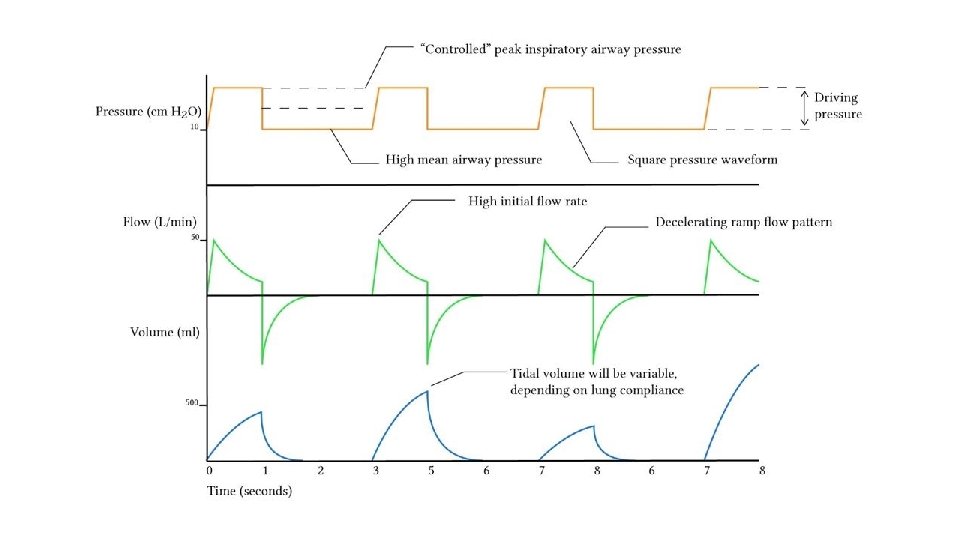

Ventilator Modes Pressure Control Ventilation Favours the control of oxygenation Advantages Disadvantages Increased mean airway pressure VT is variable and dependent upon lung compliance Increased duration of alveolar recruitment Uncontrolled volume may result in volutrauma (overdistension) Protective against barotrauma High early inspiratory flow may breech the pressure limit if airway resistance is high Work of breathing and patient comfort may be improved • Adaptive modes of ventilation (PCV-VG ; PRVC) combine advantages of pressure and volume control modes